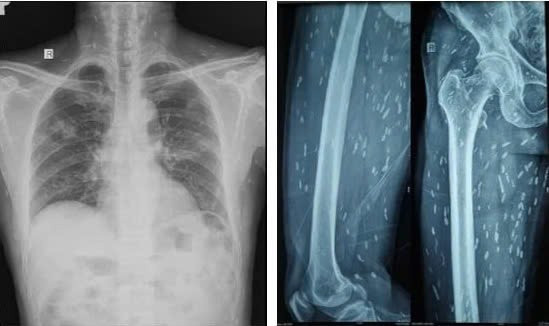

Bệnh nhân được chụp Xquang xương đùi, CT-scan ngực để tầm soát tổn thương ở cơ quan khác, phát hiện vô số nang sán dải còn sống hoặc đã bị hóa vôi “ẩn nấp” trong não, nhu mô phổi, và trong da, cơ trên toàn bộ cơ thể người bệnh.